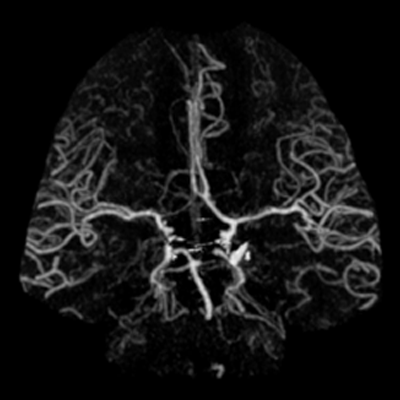

You arrive at the patient's room. You quickly examine her. Her left pupil is truly dilated and unreactive. Her right pupil is also dilated and unreactive, and also deviates to the right. She is unable to follow commands but is moving her extremities spontaneously. The right side of her body seems to be moving slightly less than her left. You escort the patient with RRT and your neurology colleague to radiology, where a non-contrast head CT and CTA head/neck are obtained.

The non-contrast head CT looks generally similar to her prior scan. There's no new hemorrhage anywhere. There's no mass effect causing midbrain compression. The vessel imaging also looks unrevealing-- a slightly hypoplastic right A1 segment, but no clear LVO in either the anterior or posterior circulation. There's no vasoconstriction.